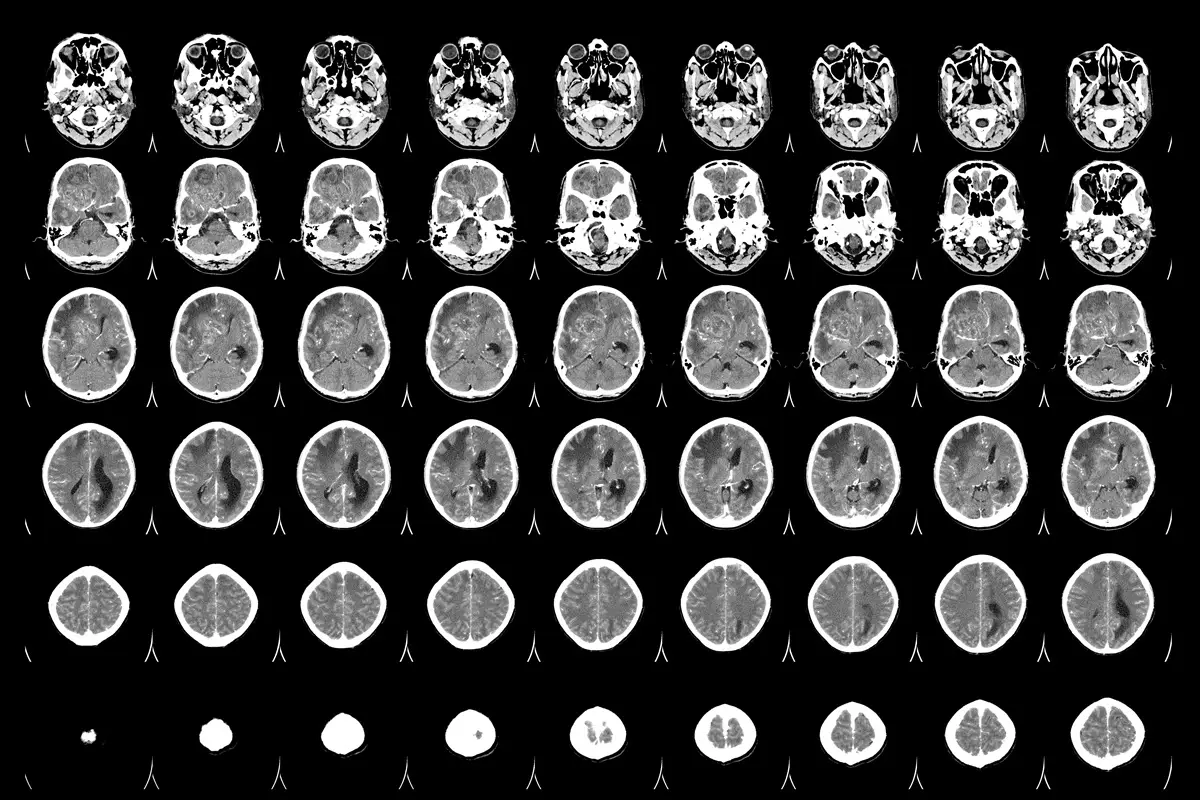

“Hay una necesidad clínica no cubierta, urge encontrar terapias específicas para la metástasis cerebral”, dice. Hasta un 30% de los pacientes de cáncer desarrollan metástasis cerebral, sobre todo de tumores de mama, pulmón, piel y colon/recto.

Los resultados del grupo del CNIO promueven un gran cambio conceptual: la metástasis cerebral es una enfermedad con entidad propia, no una mera extensión del tumor primario, como se ha entendido hasta ahora. Es un cambio que afecta a la búsqueda de tratamientos.

Los datos apuntan a que tratar la metástasis según el tumor del que procede, como se hace hoy, “es insuficiente”, dice Valiente. “Vemos que hay fármacos potencialmente efectivos para tratar las metástasis que no están necesariamente ‘encima de la mesa’ del oncólogo, porque no son los que corresponden al tratamiento del tumor primario. Nuestros hallazgos sugieren que estamos dejando escapar oportunidades terapéuticas”, asegura.